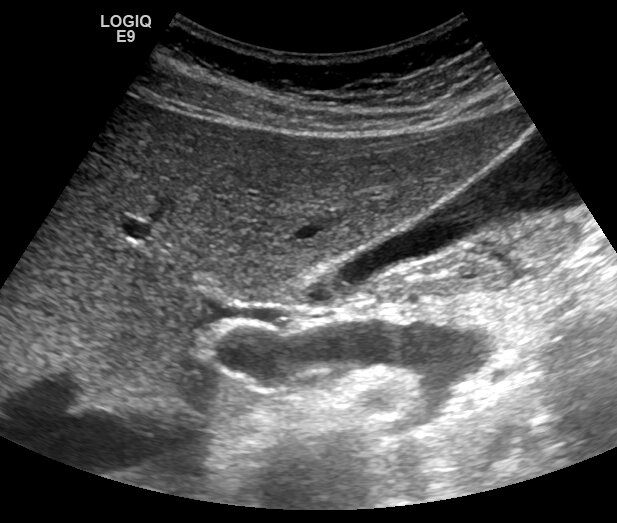

При ультразвуковом исследовании печени врач УЗД визуализирует гепатикохоледох. Зона слияния правого и левого внутрипеченочных протоков, как правило, не визуализируется, но при отсутствии расширения протоков визуализация этой зоны не имеет принципиального значения. Но иногда можно увидеть отчетливо слияние правого и левого внутрипеченочных протоков. Видео: https://dzen.ru/video/watch/66582ab24576313e323ff93d Убедиться, что это именно протоки, а не сосуды, можно при цветной допплерографии - просвет протоков не окрашивается. Видео: https://dzen.ru/video/watch/66582b051b8759059da23b61 Следует отметить, что с точки зрения анатомии, правильнее говорить не "бифуркация" а "конъюнкция", поскольку имеет место не разделение одного протока на два, а слияние двух в один.

При ультразвуковом исследовании печени врач УЗД визуализирует гепатикохоледох. Зона слияния правого и левого внутрипеченочных протоков, как правило, не визуализируется, но при отсутствии расширения протоков визуализация этой зоны не имеет принципиального значения. Но иногда можно увидеть отчетливо слияние правого и левого внутрипеченочных протоков.